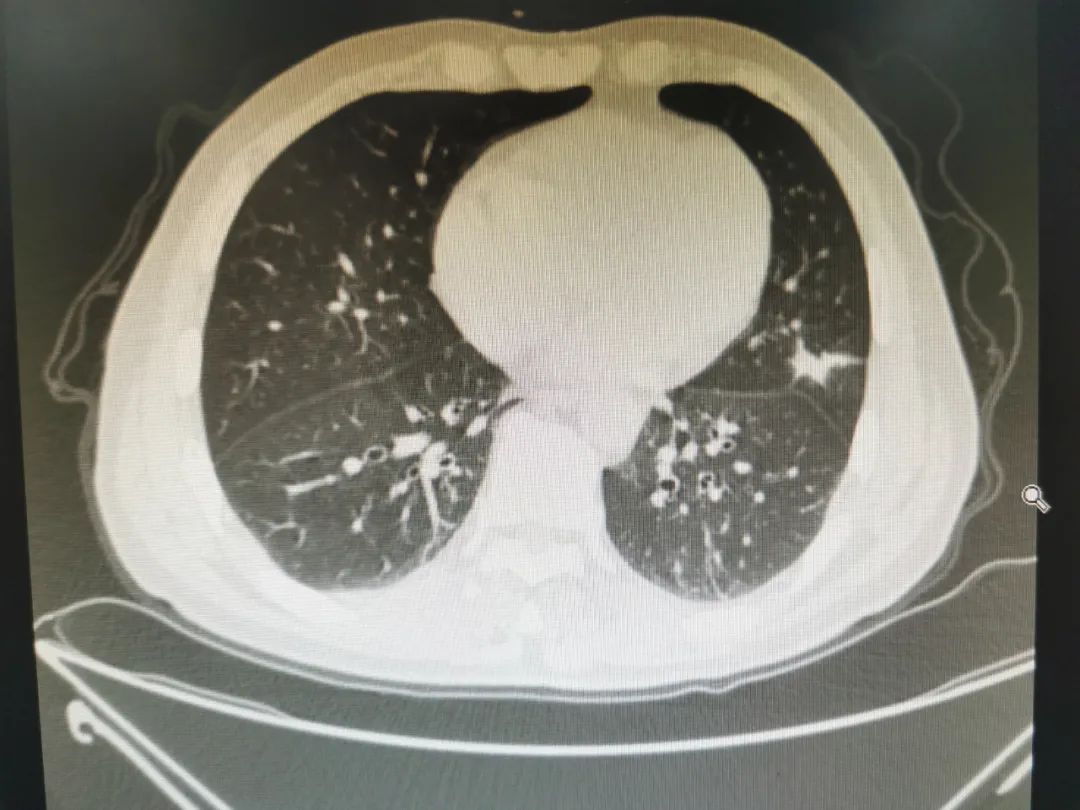

現在,假設你是一個外科醫生,你接診了一個病人,他在體檢的時候發現了左肺上葉一個實性結節,大小約22mm。

左肺上葉實性結節

你在CT上仔細看了這個結節,實性的,密度很高,有毛刺和分葉,給你的感覺很不好。 就像警察看到了吳籤,覺得這個人面露淫光、行跡猥瑣,不 像是個好人 。